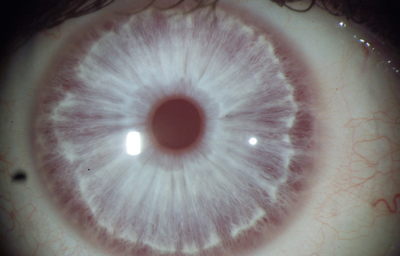

Anomalias del Estroma: Hiperplasia, Hipoplasia

Hiperplasia

Archivo fotográfico Dr. Francisco Barraquer.

Hipoplasia

Archivo fotográfico Dr. Francisco Barraquer.